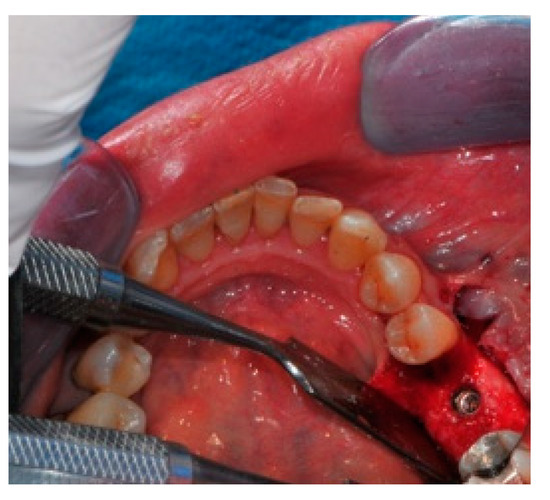

- Flap design: Soft tissue management should be as accurate as possible. The design of the flap should ensure a tension-free primary closure of the wound even after voluminous grafting of the defect. One option (preferred especially in wide vertical defects) is the execution of the so-called “poncho” flap. This technique includes a high vestibular incision of the mucosa, muscle and periosteum in order to undermine the preparation of the flap and to achieve its mobilization, followed by a deep incision in the buccal area with two additional vertical incisions that are performed at an appropriate distance from the occlusal area and the site of augmentation. After the incision, the preparation of a muco-periosteal flap and the remotion of scar tissue, a full thickness flap is raised until the bone defect is uncovered [17,18,19,20]. Finally, the positioning of the customized titanium mesh is passively tested to evaluate its fit intra-operatively (Figure 2, Figure 3, Figure 4 and Figure 5).

- Preparation of the receiving site: The exposed bone is cleaned from all of the remaining soft tissue and it is then prepared with multiple perforations using a small ball bur; this procedure is known as “bone refreshing” and it is performed to expose the cancellous portion of the residual bone, which shows a great osteo-genetic potential (Figure 6).